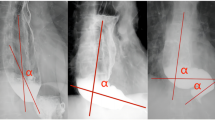

Our surgical procedure for esophagectomy is reported elsewhere9,10,11. Briefly, our procedure for endo-to-endo, layer-to-layer handsewn anastomosis is as follows. Stumps of the esophagus and gastric conduit are grasped with straight grasping forceps. To avoid interrupting blood flow or crushing the tissues, anastomotic lines are set under the forceps (Fig. 4A). After cutting the posterior wall muscular layer with a scalpel (Fig. 4B), the muscular layer is interrupted sutured using VICRYL Plus (ETHICON). The mucosal layer under the straight grasping forceps is then cut all the way around using scissors, and the inner cavity is opened. The posterior wall mucosal layer is running sutured to the anterior wall mucosal layer using PDSII or LACLON while monitoring blood flow in the esophagus and gastric conduit (Fig. 4C). Ligation of the running suture is made in the submucosal layer to avoid placing the ligation in the inner cavity (Fig. 4D). Finally, the anterior wall muscular layer is interrupted sutured using VICRYL Plus (Fig. 4E). After washing the anastomosis with warm saline, the gastric conduit is pulled and straightened via an abdominal wound.

Our procedure for layer-to-layer handsewn anastomosis. Stumps of the esophagus and gastric conduit are grasped with straight grasping forceps. To avoid interrupting blood flow or crushing the tissues, anastomotic lines are set under the forceps (A). After cutting the posterior wall muscular layer with a scalpel (B), the posterior wall muscular layer is interrupted sutured using VICRYL Plus (ETHICON). The mucosal layer is then cut all the way around under the straight grasping forceps using scissors, and the inner cavity is opened. The posterior wall mucosal layer is running sutured to the anterior wall mucosal layer using PDSII or LACLON while monitoring blood flow in the esophagus and gastric conduit (C). Ligation of running suture is made in the submucosal layer to avoid placing the ligation in the inner cavity (D). Finally, the anterior wall muscular layer is interrupted sutured using VICRYL Plus (E).